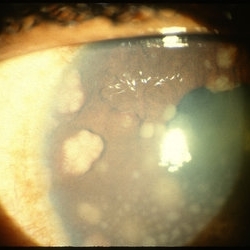

Busacca nodules

May 2 2013 by Henry J. Kaplan, MD

Typical Busacca iris stromal nodules in sarcoid uveitis; notice the ps formation.

Condition/keywords: busacca nodulaes, granulomatous uveitis, iris nodules, sarcoid bussaca iris nodules